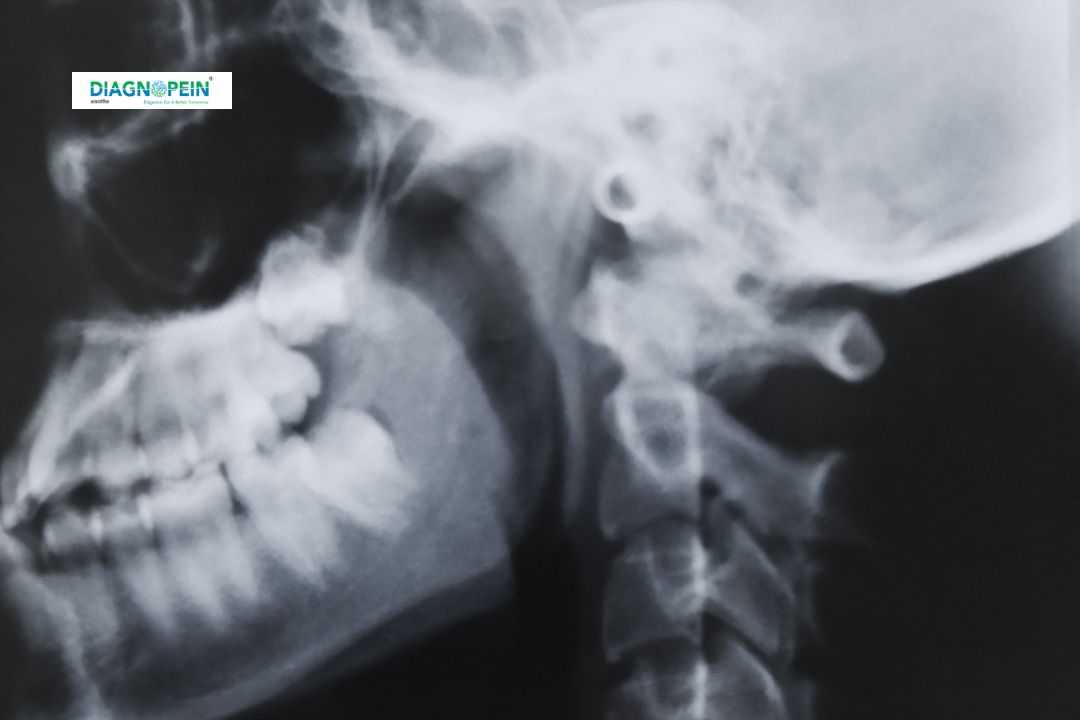

PNS View (1 film), also called a Paranasal Sinus X-ray, is a simple and effective radiological test used to evaluate the health of your sinus cavities. At Diagnopein Radiology Center, Karad, our advanced imaging tools ensure clear visualization of the sinuses, especially for diagnosing infections, sinusitis, or structural blockages. This test, also known as the Waters View X-ray Karad 1 film, provides a single, high-quality radiograph of your paranasal sinuses.

The PNS View X-ray helps your doctor visualize air-filled spaces around your nose, eyes, and forehead. This imaging test can identify sinus infections, nasal polyps, fractures, or blockages in nasal passages. Choosing Diagnopein Karad for your PNS View ensures accurate interpretation by expert radiologists and timely reporting.

Getting a Paranasal Sinus X-ray 1 film Karad is simple and quick. No fasting or special preparation is required. You’ll be asked to remove any metal accessories like earrings or glasses. During the test, a radiographer positions your face at an angle to capture the Waters view X-ray Karad 1 film, targeting the maxillary and frontal sinuses.

3. A single exposure (1 film) is taken in Waters or occipitomental view.